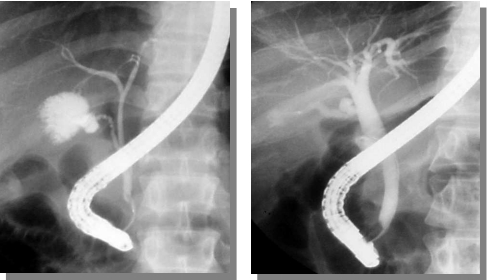

内镜下逆行胰胆管造影术(ERCP)是指将十二指肠镜插至十二指肠降部,找到十二指肠乳头,由活检管道内插入造影导管至乳头开口部,注入造影剂后X线摄片,以显示胰胆管的技术。诊断性ERCP主要用于怀疑有胆系疾病、胰腺疾病等情况的诊断。

在ERCP基础上,还可进行十二指肠乳头括约肌切开术(EST)、内镜下鼻胆汁引流术(ENBD)、内镜下胆汁内引流术(ERBD)等治疗操作。此类内镜技术具有创伤相对较小、恢复较快、住院时间相对缩短等特点。